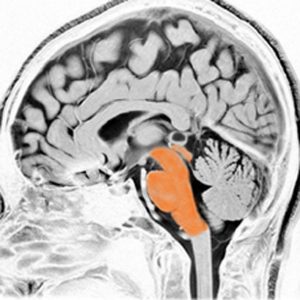

これは脳の中心部を縦切りにした写真です。脳幹部は上から順に,中脳 midbrain (黄色),橋 pons(オレンジ),延髄 medulla oblongata(ピンク)と呼ばれます。

共通しているのは脳幹部の障害では意識障害が出ることです。中脳脚から延髄腹側まで錐体路という運動神経を司る経路があり,これが障害されると片麻痺や四肢麻痺がでます。脊髄視床路の障害では全身の感覚障害となります。主として背側損傷では運動失調も出ます。脳神経麻痺,眼球運動障害,嘔吐などさまざまで複雑な症候が出る重要な部位です。